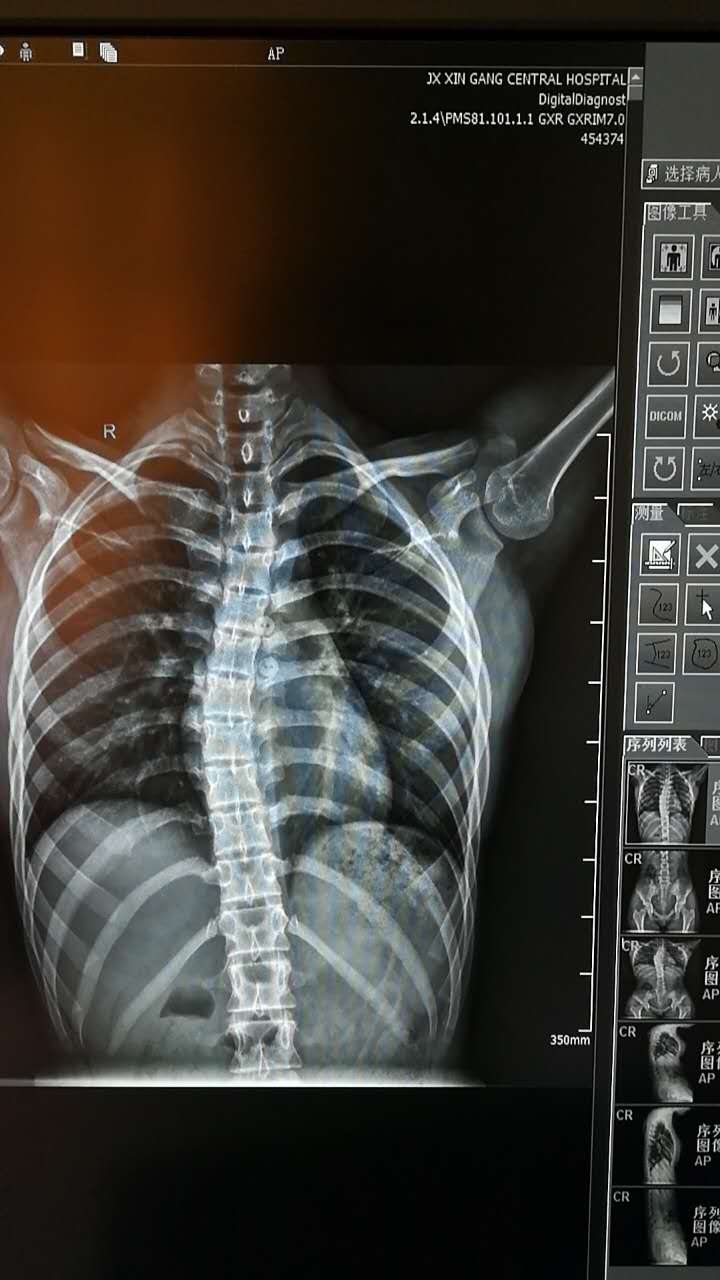

双板DR全数字摄影系统功能强大,性能优越,DR 平板探测器(FPD )因具有量子吸收效率高、高分辨率,检查部位主观随心调节等优良性能而得到广泛应用。利用常规的摄影参数连续采集多幅图像,然后再拼接合成的技术,DR专业应用培训工程师戏称:会飞的DR.。例如,双下肢全长图像拼接检查利用图像拼接软件显示从髋关节至踝关节的下肢病变情况, 对髋关节角度的测量, 髋和膝关节矫形手术, 人工关节置换术等有着重要的指导价值。数字化影像双下肢拼接的作用主要是配合临床对全下肢进行应力线测量, 对临床的手术特别是膝关节置换术提供必要的手术依据。

医院放射科开展的DR全景成像技术是基于全自动拼接技术,能有效地满足临床应用的需求,减少患者检查次数,有效降低辐射等副作用的影响。我院致力于不断开展新技术,提高业务能力,竭诚为患者减轻痛苦、降低检查费用,最大化患者利益。